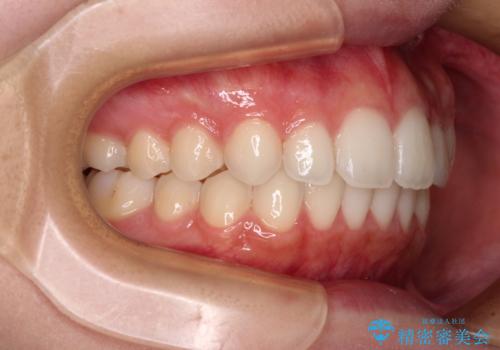

【モニター】前歯のクロスバイトをインビザラインで治療

- 前歯のデコボコとクロスバイトを気にして来院された患者様です。

上顎側切歯(上の真ん中から2番目の歯)が舌側転位している場合、インビザラインでは仕上げきれないことが多く、更には無理して動かそうとすると歯髄壊死を起こすリスクが高いと言われています。

今回は、ワイヤー装置を併用することなく、インビザライン単体で矯正治療を行うこととしました。

インビザライン特有の、奥歯の咬み合わせの問題もなく、しっかりと歯列を改善することができました。

舌側転位している上顎側切歯(内側に引っ込んでいる真ん中から2番目の歯)は、インビザラインが最も移動を苦手とする歯であり、これ以上の改善を望まれる場合にはワイヤー矯正、あるいはワイヤー矯正の併用をお勧めいたします。